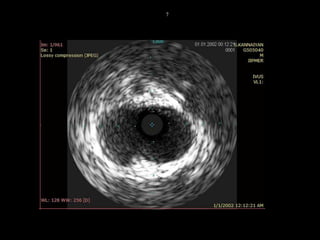

57/M ,old IWMI, CSA3

IVUS

FFR = 0.91

LM STENTING DEFERRED !!!

 Characteristic three-layered

appearance (bright-dark-bright)

 Spillover effect (blooming)

 Normal vessel – intima maynot be

seen

 Atherosclerotic vessel – media

may not appear distinct

 20-45 MHz

 100-200 µ resolution

 4-8 mm beam penetration